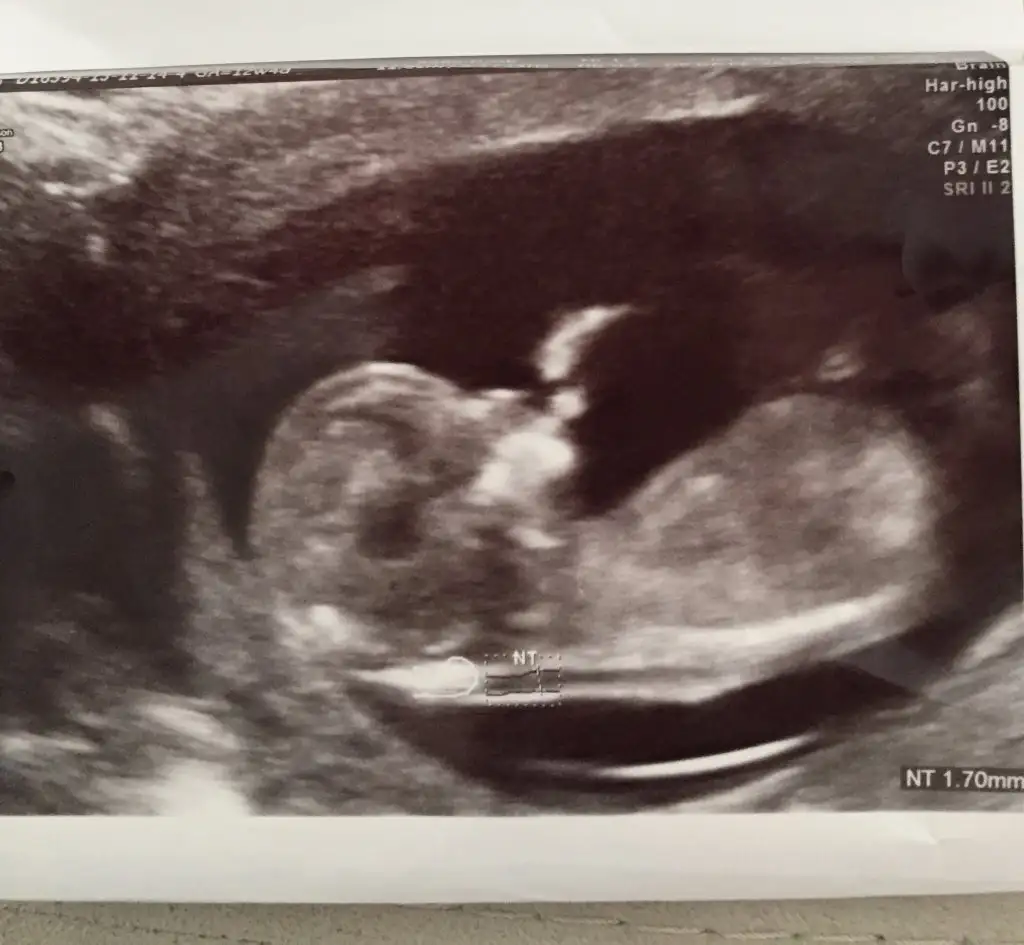

dr soylemeden siz gorun genital nub teorisi ( bebegin cinsiyeti)

Kizlar arkadasimin bebeğine de bakar misiniz....anlayamadik biz